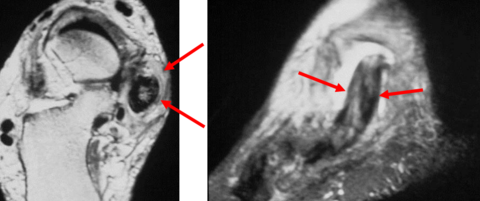

What does the arrow show? What could this be? | Teardrop-shaped hypointense lesion in third interspace. Could be morton's neuroma |